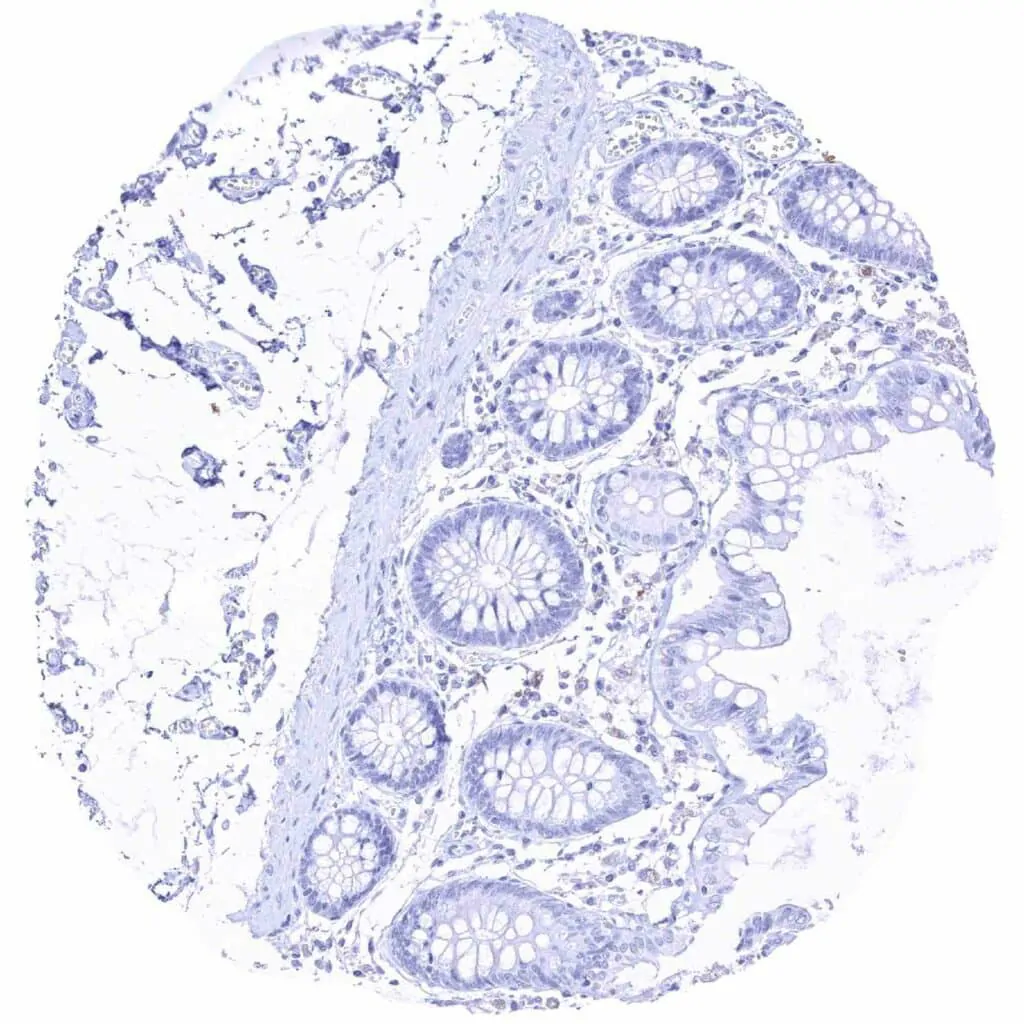

Colon descendens, mucosa

Rectum, mucosa